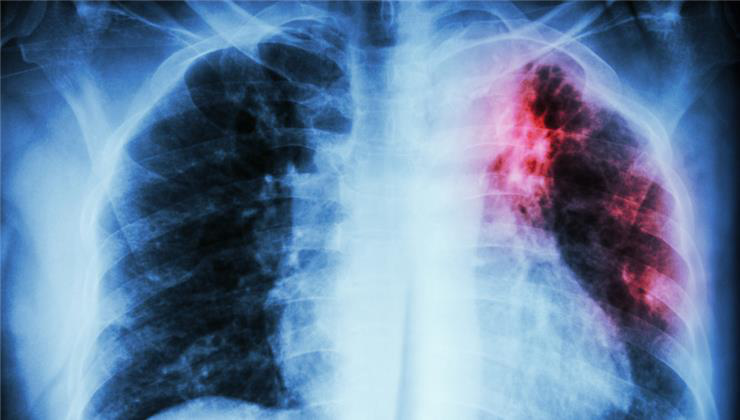

A leggyakrabban érintett terület a tüdő, amelyen születéskor még nem érzékelhető semmilyen elváltozás. Az idő múlásával a sűrű nyák folyamatosan csökkenti az aktív légzőfelületet, ami befolyásolja a gázcserét - ennek következménye az alacsonyabb véroxigén és a magasabb szén-dioxid szint. Ez a napi aktivitás csökkenéséhez vezethet, gyakran észlelhető továbbá a dobverőujjak tünete is. Ez azt jelenti, hogy a kéz- és/vagy lábujjak végei megnagyobbodnak, és a körömágynál a normális hajlási szög megszűnik.